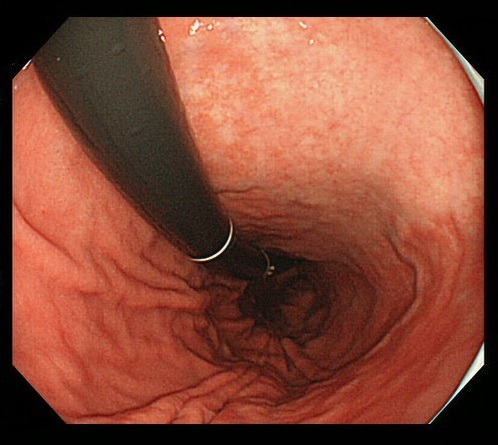

2. 내시경 중 조직 채취

의사는 내시경 카메라를 통해 위 내부를 관찰하면서 이상 부위를 발견하면, 내시경 끝에 부착된 작은 겸자(Forceps)를 이용해 점막의 일부를 매우 소량 떼어냅니다. 일반적으로 통증은 거의 없으며, 일부 환자는 ‘찌릿’한 느낌 정도만 느낄 수 있습니다. 한 번의 검사에서 2~5개 정도의 조직을 채취하는 것이 일반적입니다.